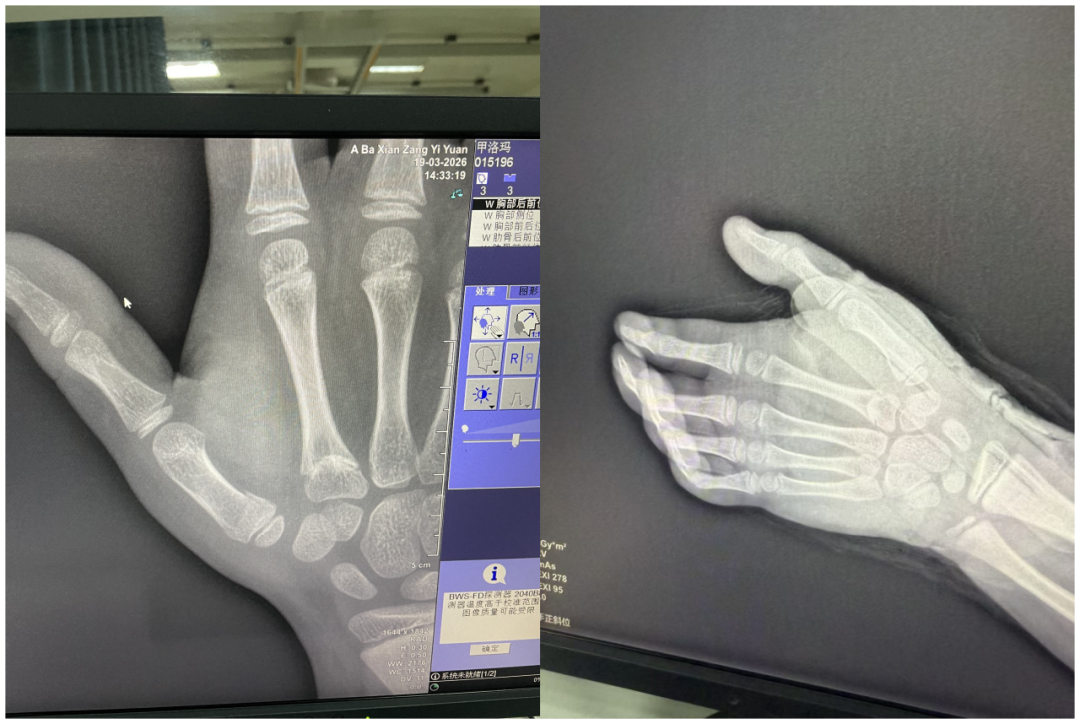

27天前,3月19日14时30分,旦增仁青在校园不慎摔倒,右手撑地致剧烈疼痛。家人第一时间送往阿坝县藏医院,急诊DR检查确诊为第一掌骨基底部骨折。儿童掌骨骨折若处置不当,可能影响手部发育与功能,诊疗刻不容缓。

经详细问诊、体格检查与影像评估,专家团队明确诊断,并向家属细致讲解手术与保守治疗的优劣。家属充分沟通后,坚定选择中医保守治疗。

王朝阳医生与尕让俄惹医生紧密协作,实施骨折手法整复术。运用何天佐传统中医正骨手法,牵引、折顶、按压、对位一气呵成,复位即刻复查DR显示:骨折对位对线良好,达到临床复位标准。

4月14日复诊显示:骨痂生长良好,局部无压痛,拆除夹板后拇指功能恢复理想。为巩固疗效,继续予续断接骨散、止痛壮骨散特色中药外敷。